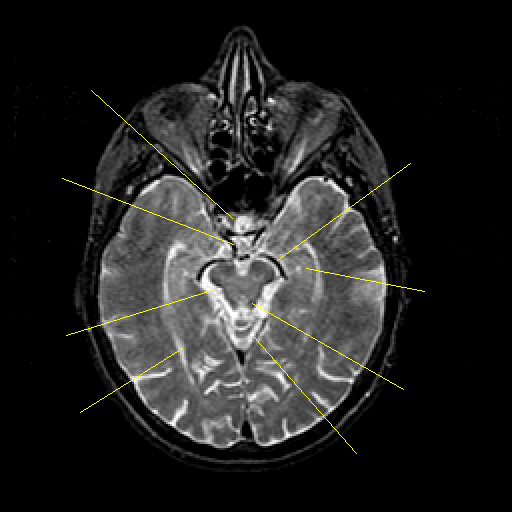

T2-weighted structural MR: Slice 21

Slice 21

Pointers

Labeled